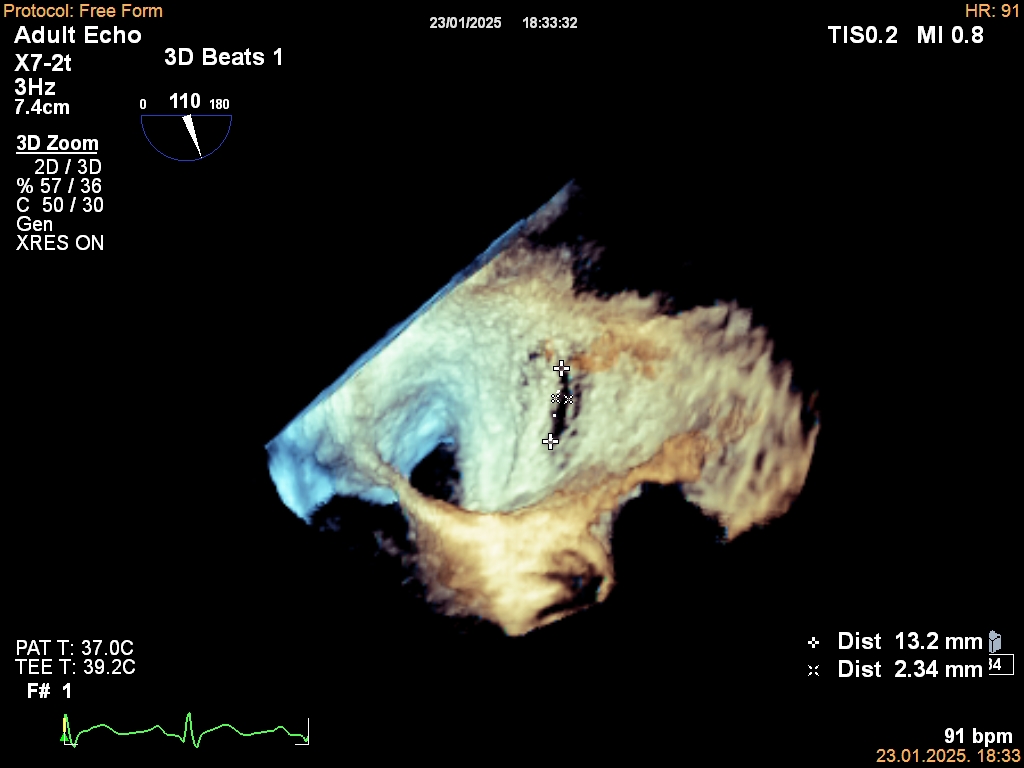

- Prednosti 3D transezofagealne ehokardiografije u dijagnozi i prognozi infektivne endokarditisa

(⬇️ Preuzmite PDF) - AI EKG za predikciju srčane slabosti s reduciranim EF: pregled i meta-analiza